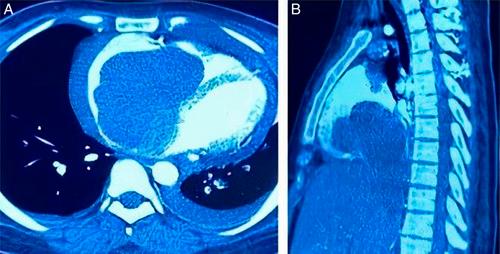

A 26-year-old female presented to the emergency room with persistent abdominal pain, ascites, lower limb edema, and an acute episode of dyspnea. Abdominal computed tomography revealed a lesion in the right cardiac cavity that resembled an intracardiac thrombus. Transthoracic echocardiography showed a large heterogeneous mass in the right atrium protruding into the right ventricle and a large thrombus interfering with inferior vena cava flow. The patient underwent cardiac surgery to remove the atrial mass, and histopathologic examinations confirmed the diagnosis of atrial myxoma.

一名26岁女性因持续性腹痛、腹水、下肢水肿及急性呼吸困难发作就诊于急诊室。腹部计算机断层扫描显示右心腔内有一病变,类似心内血栓。经胸超声心动图显示右心房内有一巨大不均匀肿块突入右心室,并有一巨大血栓干扰下腔静脉血流。患者接受了心脏手术以切除心房肿块,组织病理学检查确诊为心房黏液瘤。